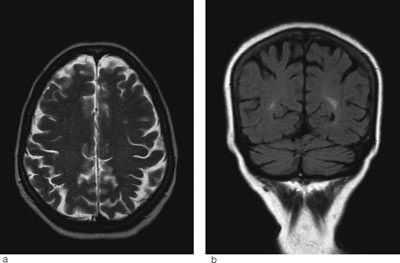

Det ble vurdert ytterligere behandling av de mulige utløsende årsakene, men blodtrykket, infeksjons- og nyreprøver normaliserte seg imidlertid spontant det første døgnet, slik at ingen videre behandling ble gitt. Pasienten ble raskt bedre, og etter noen dager fikk hun gradvis synet tilbake. Paresene bedret seg langsomt, og hun var oppegående etter noen uker. Ved kontroll etter fire måneder var hun helt symptomfri, og det var ingen patologiske funn ved nevrologisk undersøkelse. MR cerebrum viste at ødemforandringene hadde gått helt tilbake (fig 2a-b).

Ved MR cerebrum er det som regel karakteristiske funn ved posterior reversibel encefalopati-syndrom med vasogent ødem parietooksipitalt bilateralt (5). I uttalte tilfeller, som hos vår pasient, kan man se slike forandringer i hjernestammen og cerebellum, sjeldnere i fremre deler av cerebrum (6). T2-vektede MR-bilder og FLAIR-sekvenser er sensitive for ødem, som vises som høysignalforandringer (fig 1a-b).